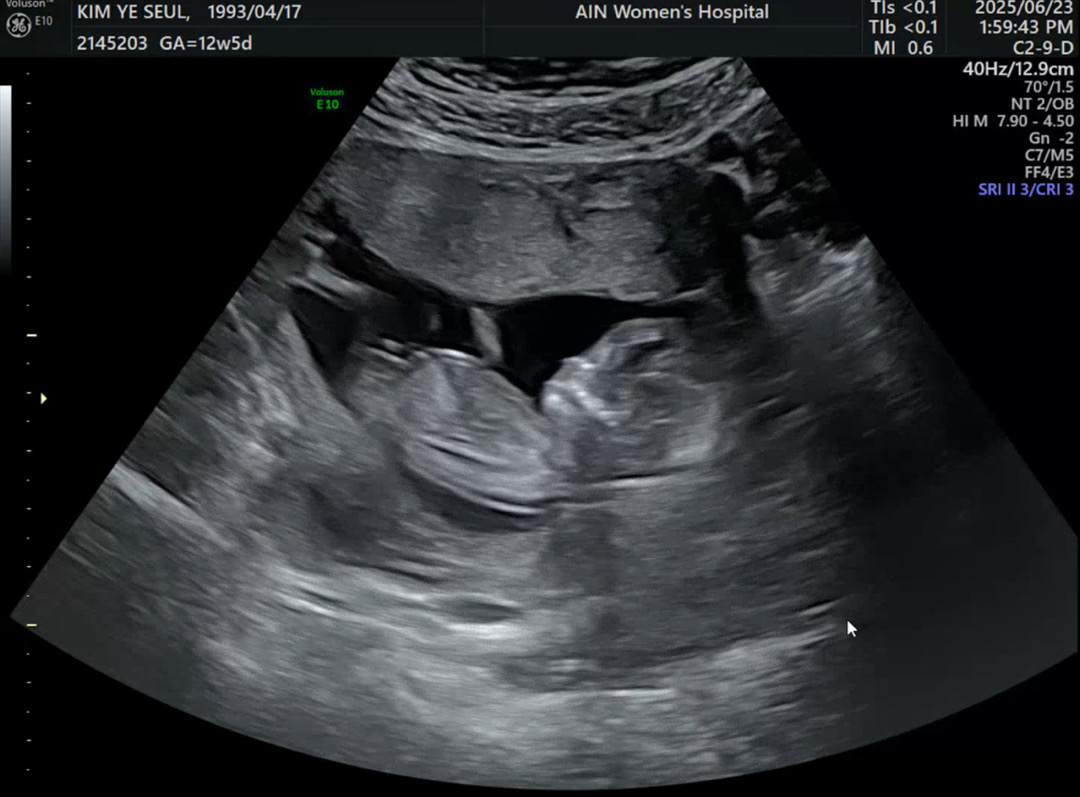

12주5일 각도법

선생님이 힌트 주셨는데 남편은 믿을수 없다며 각도법 잘 보시는 고수님들께 물어보자고 하네여 ㅎㅎㅎㅎㅎ 고수님들 한번씩만 의견 부탁 드릴게여 ❤️

딸각도로 보여요